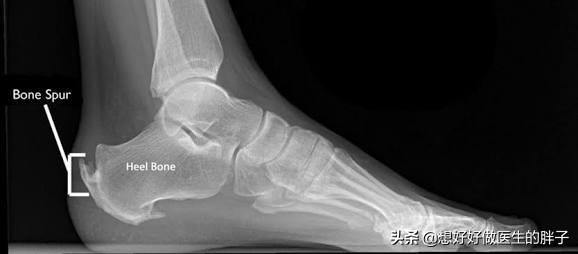

第三,还有一些骨刺,虽然不会影响患者的活动范围,也不会造成神经的卡压,但是会造成患者活动性的疼痛,就是说只要一活动就会疼痛。比如跟骨骨刺,虽然不是占全部的因素,只占30%左右,但是确实有着一部分患者是因为骨刺导致的活动性疼痛。#清风计划# #青云计划#